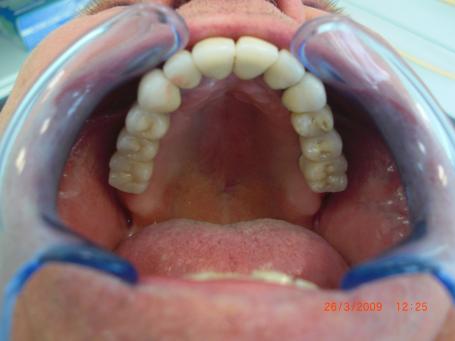

6°) Couronnes céramiques sur implants

3 couronnes unitaires sont réalisés d’un coté et un bridge de 3 dents est réalisé de l’autre.